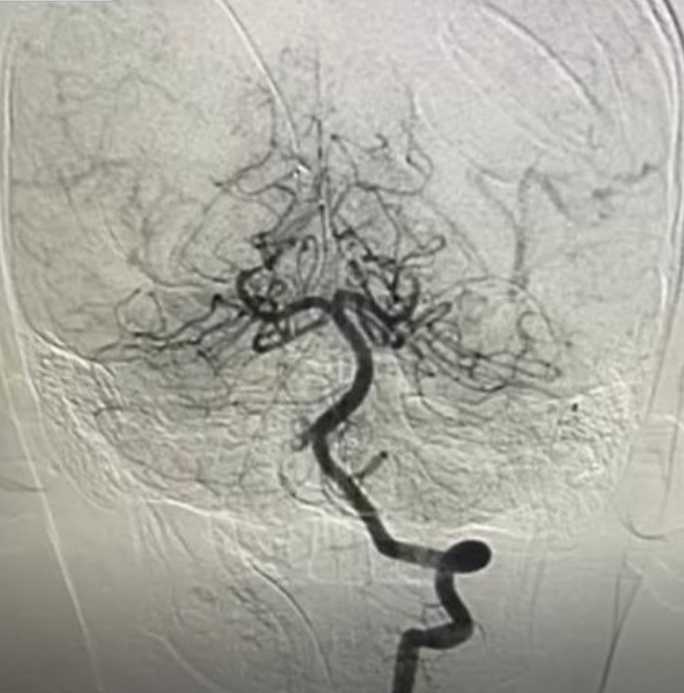

Tại đây, các bác sĩ đã tiến hành MRI não và cột sống cổ, ghi nhận tổn thương nhồi máu cấp vùng hành não. Huyết khối gần như hoàn toàn động mạch đốt sống phải, nguy cơ diễn tiến nặng hơn nếu không can thiệp kịp thời.

Ngay lập tức, các bác sĩ đã hội chẩn liên khoa, thống nhất chỉ định chụp DSA để đánh giá mức độ huyết khối, để có phương pháp can thiệp kịp thời.

BSCKII Trần Công Bảo Phụng cùng ê-kíp đã tiến hành thông tim mạch cấp cứu ngay cho bé, luồn ống thông theo đường động mạch đùi đến động mạch đốt sống phải, kết hợp dùng tiêu sợi huyết tại vị trí huyết khối và dùng dụng cụ chuyên biệt hút huyết khối ra ngoài.

Sau can thiệp, trẻ tỉnh táo, tiếp xúc tốt, sinh hiệu ổn, động mạch tái thông hoàn toàn, tưới máu não tốt. Sau đó, bé được chuyển về khoa Hồi sức ngoại, chức năng vận động cũng hồi phục dần. Sau 1 tuần, bé đã có thể vận động gần như bình thường.